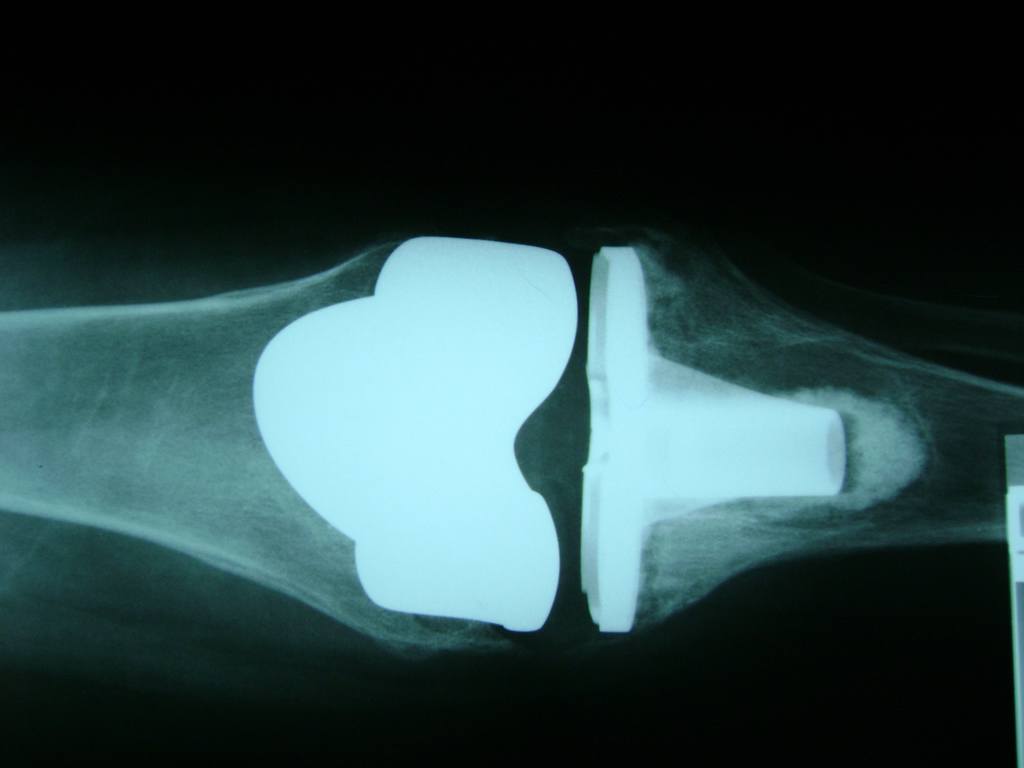

Cirugía de Tibia y Peroné

La artroscopia de rodilla es un cirugía en el cual la estructura interna de la articulación es examinada ya sea para realizar un diagnostico o para realizar un tratamiento, este procedimiento se realiza utilizando un instrumento parecido a un pequeño tubo llamado artroscopio.